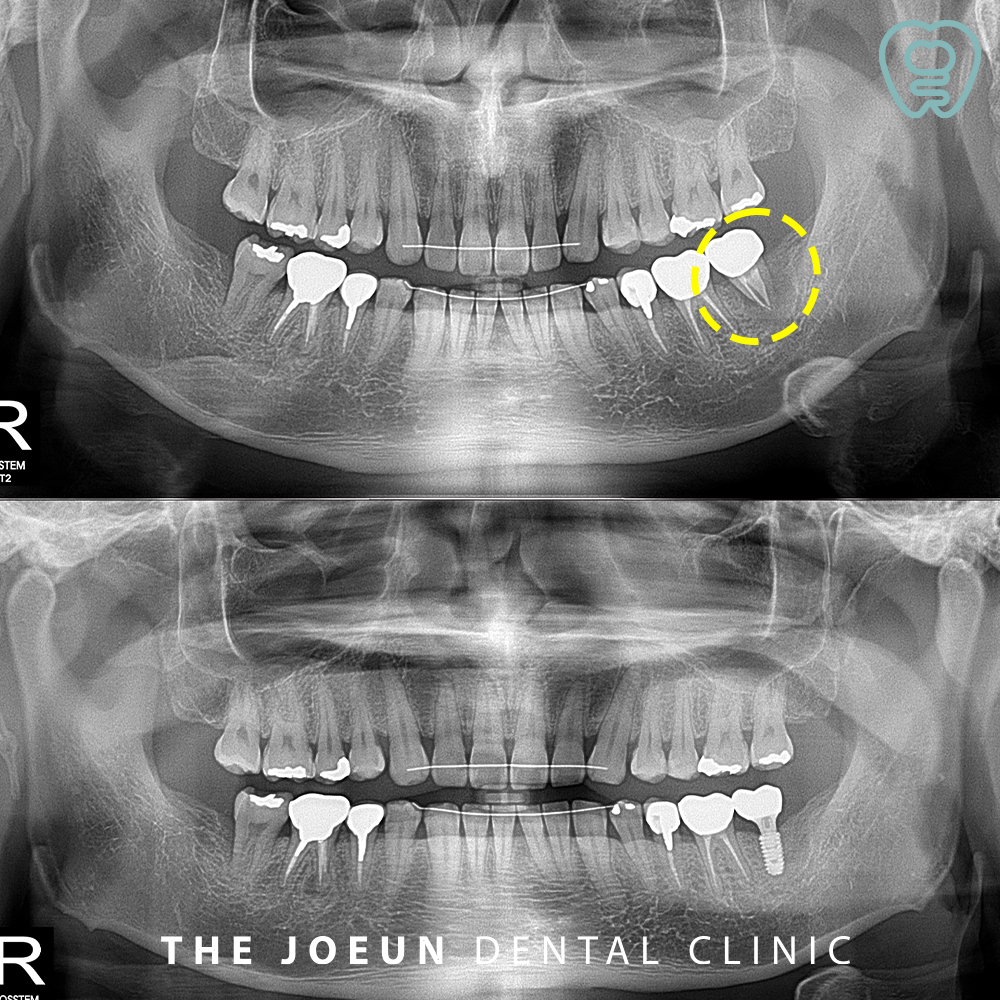

오늘은 커다란 치아 뿌리 염증으로 인해 발치 후 많은 양의 뼈이식 후 임플란트 식립을 진행하신 환자분을 소개해 드리려고 합니다.

환자분께서는 정기 검진을 오셨다가 왼쪽 아래 신경치료 후 씌워둔 치아의 커다란 염증을 알게 되셨는데요. 가끔씩 피곤할 때 잇몸이 붓는 것 이외에는 불편함이 없으셨기 때문에 염증이 커다랗다는 설명을 들으셨을 때 매우 놀라셨습니다. 이미 잇몸뼈가 많이 녹은 상태라 발치 후 뼈이식을 하여 잇몸뼈의 회복 상태를 본 뒤 임플란트 식립을 진행하기로 계획을 수립하였습니다.

가장 먼저 원인이 되는 치아를 발치하고 뼈이식을 진행하였습니다.

약 3개월 후의 사진입니다.

이후 임플란트 식립을 진행하였는데요.

최종 보철 후의 사진입니다.